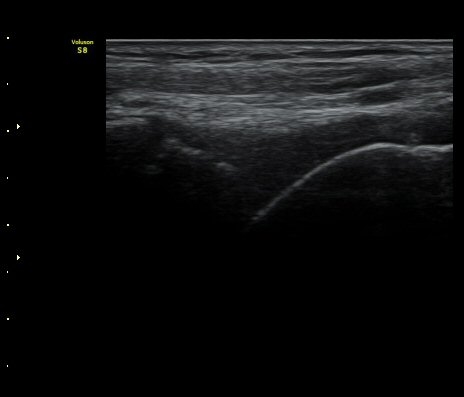

¹ß¸ñ°üÀý Á¾´Ü¸é°Ë»ç¿¡¼­ °üÀý³» ¼ö¾×Àú·ù°¡ °üÂûµÈ´Ù(±×¸² 1).

Àü°Å°ñºñ°ñÀδë Á¾´Ü¸é°Ë»ç»ó Àδë ÀδëÀÇ Àú¿¡ÄÚ ºÎÁ¾°ú ºñ°ñ

ºÎÂøºÎ ¹Ì¼¼ °ß¿­°ñÀýÀÌ °üÂûµÈ´Ù(±×¸² 3, 4).